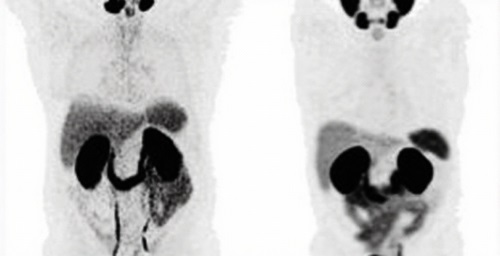

神經內分泌腫瘤與PRRT治療